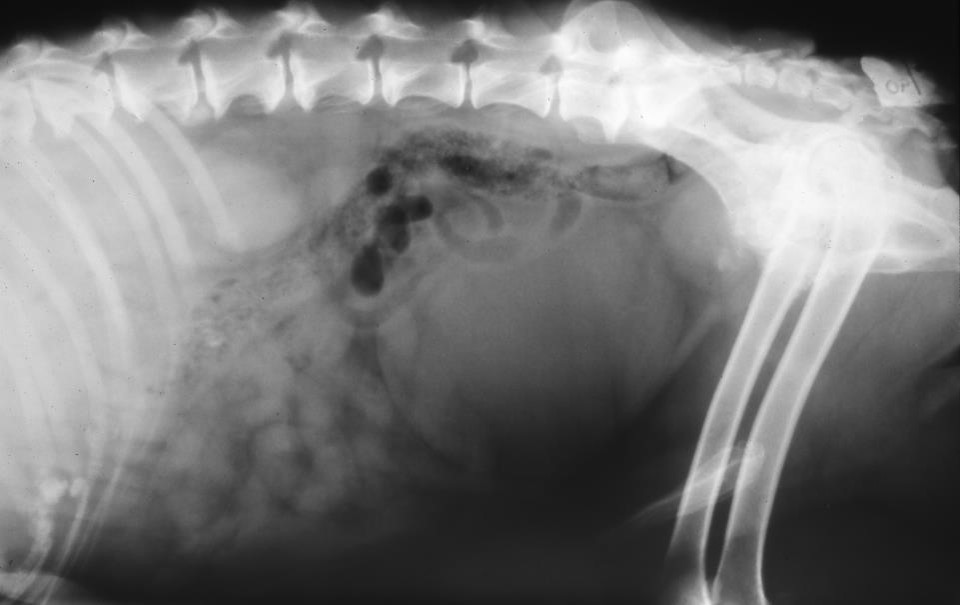

What can be seen here?

2 ST sections in cd abdo

Which structures do you think are affected?

Prostate

Bladder – big and tense

Urethra

Don’t forget spinal disease in a large bladder